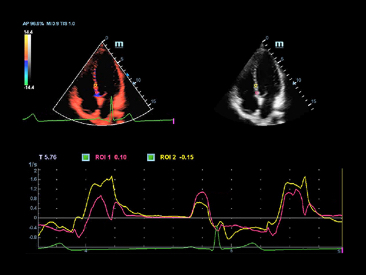

Fortgeschrittener Echo-Boost

Mindrays konsekutiver Durchbruch hin zu allerbester Ultraschall-Bildgebung.